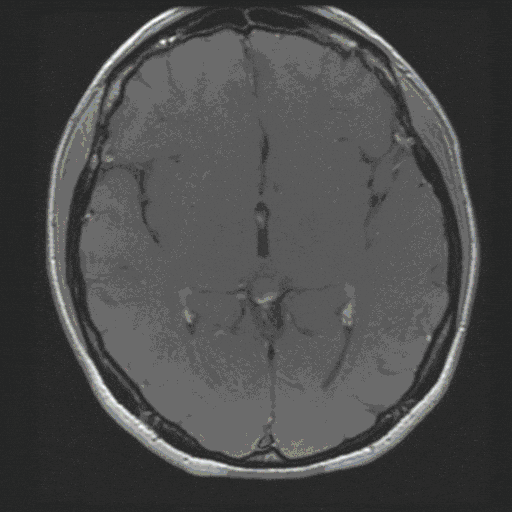

Acoustic neurinoma (actually vestibular schwannoma) is a benign tumor of the cerebellopontine angle. It can grow considerably in size due to its slow growth, thereby threatening the brain stem and its cranial nerves.